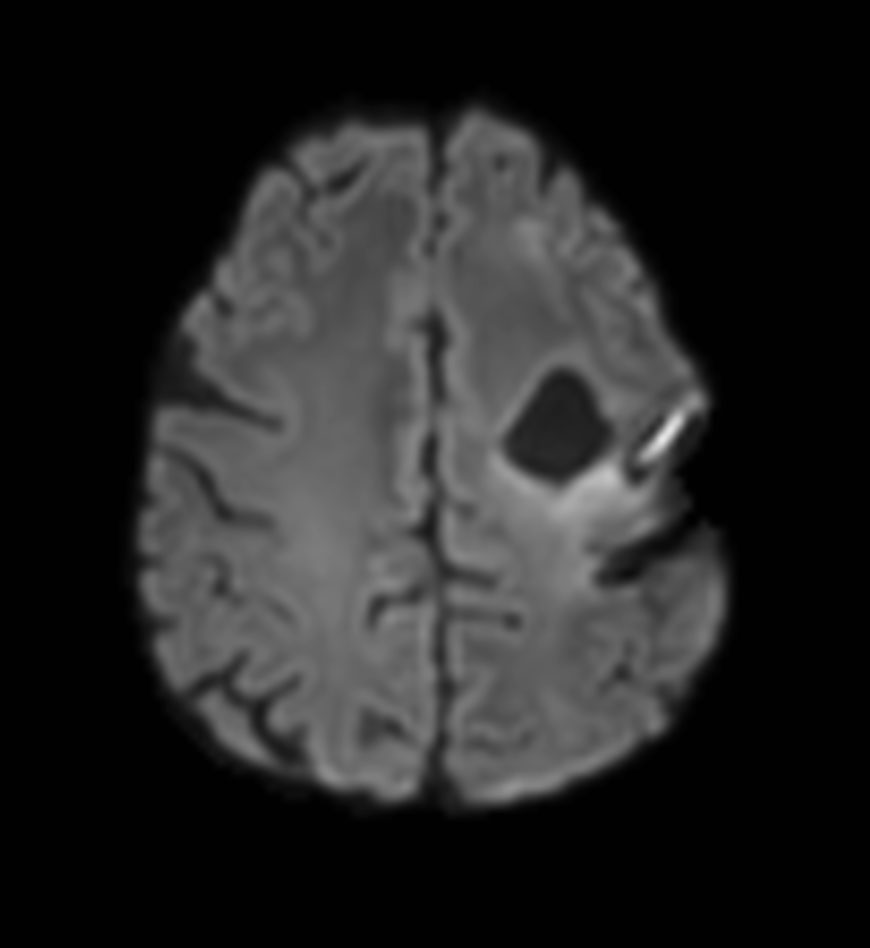

Axial DTI (b1000)